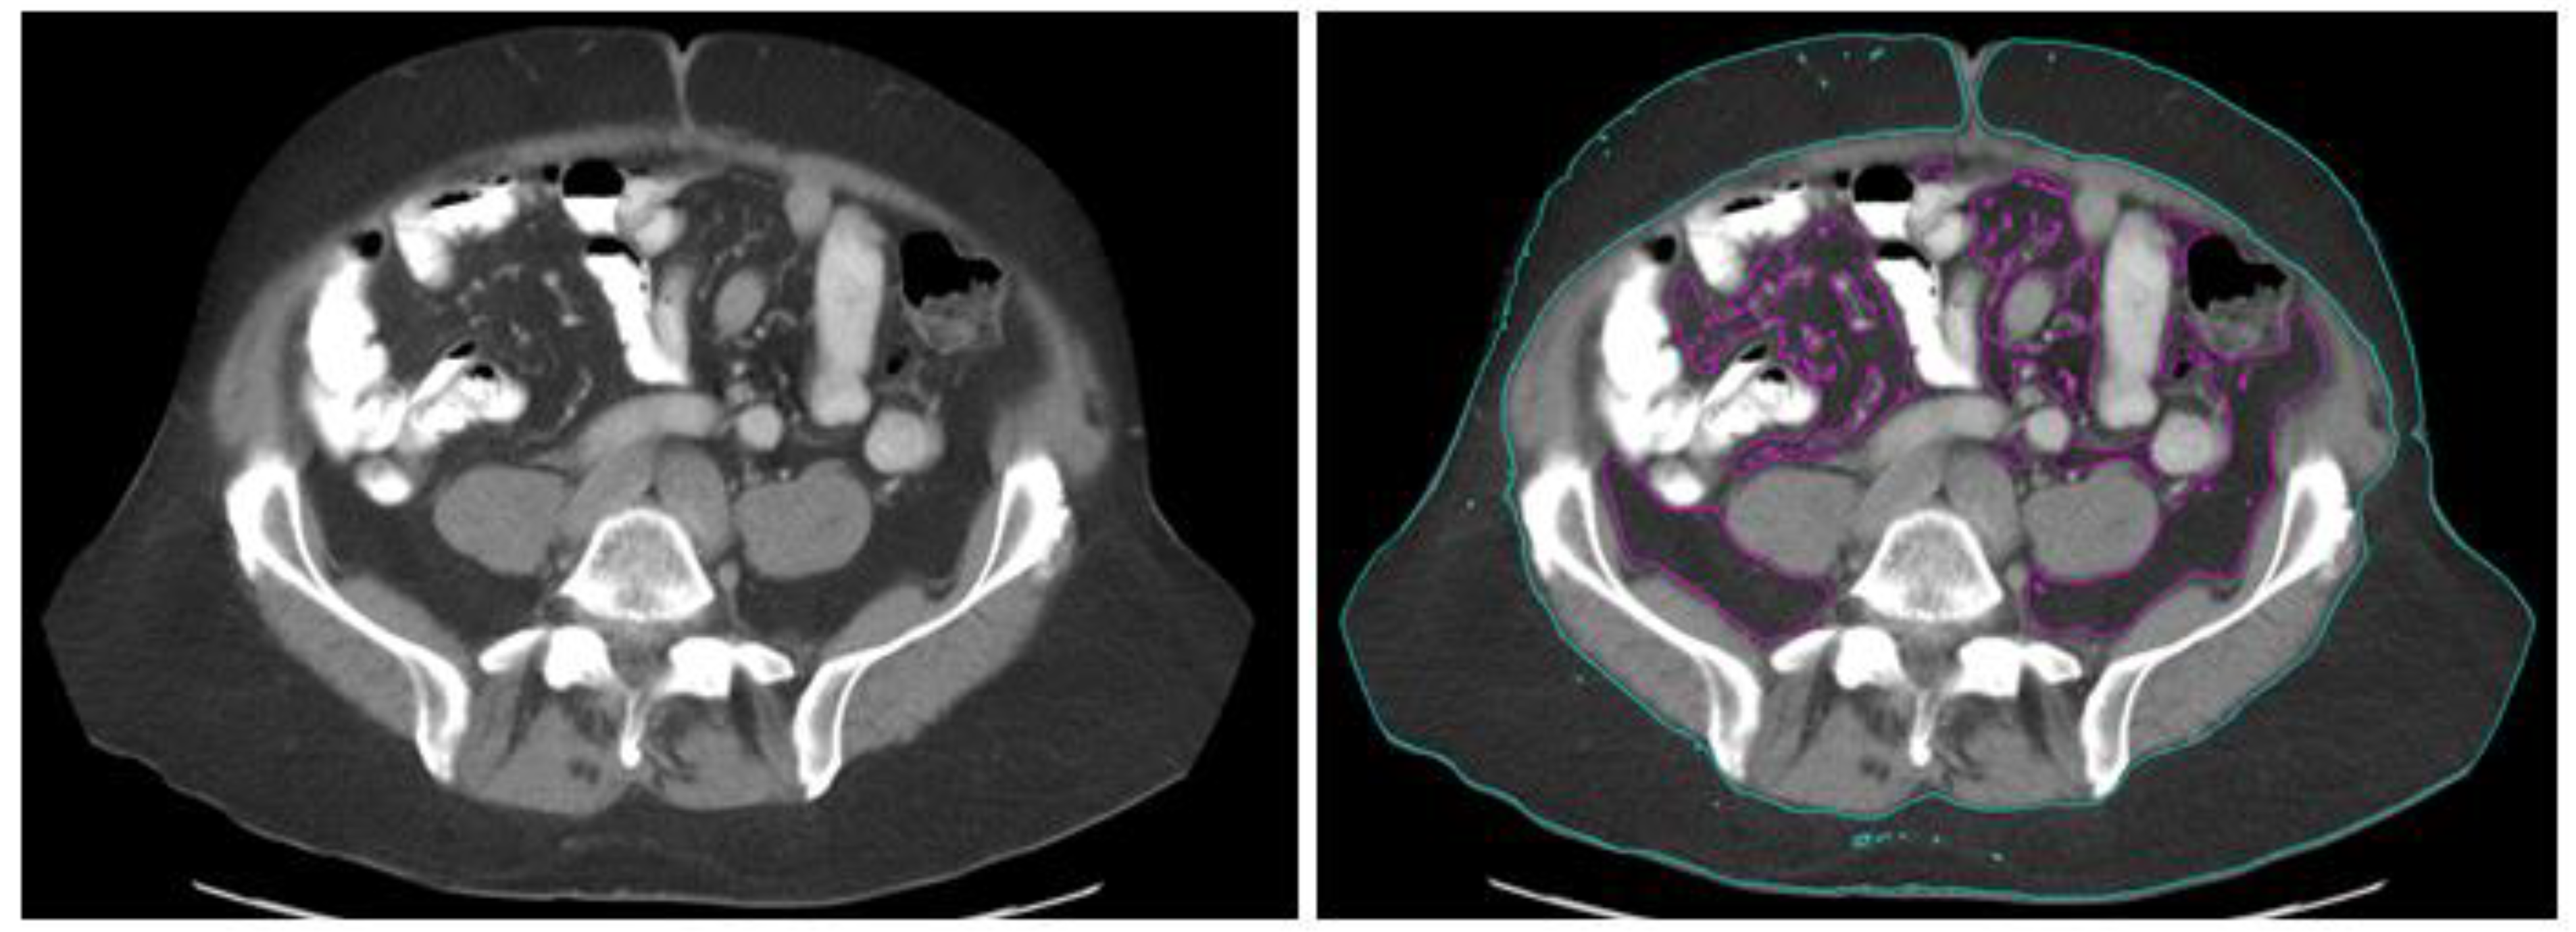

2.3. Obesity Measurement